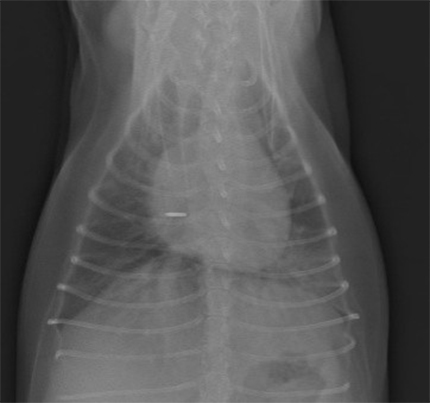

- 胸部X線検査にて、心陰影の拡大および左肺後葉領域の不透過性亢進像が認められた。

明らかな腹水貯留は認められなかった。 - 心エコー図検査にて、僧帽弁の逸脱とそれに伴う僧帽弁逆流が認められた。